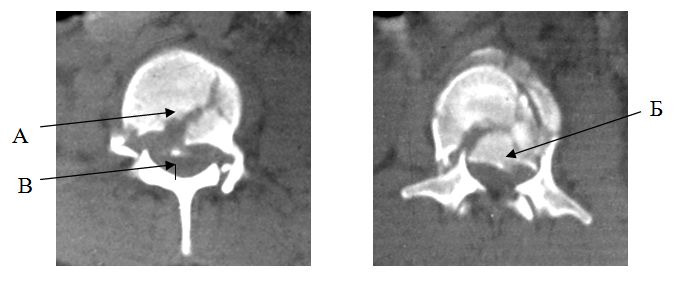

Данные компьютерной томографии используются для уточнения характера костных повреждений тела позвонка, а также оценки состояния костных структур задней колонны. Признаками взрывного перелома являются:

- наличие повреждения средней колонны (рис. 5А)

- наличие фрагментов тела позвонка в позвоночном канале (рис. 5Б)

- сужение переднезаднего размера позвоночного канала (рис. 5В)

Перечисленные признаки могут встречаться как по отдельности, так и вместе. Выполнение компьютерной томографии наиболее целесообразно при взрывных и компрессионных переломах позвонков.

|

| Рис. 5. КТ признаки взрывного перелома тела позвонка |